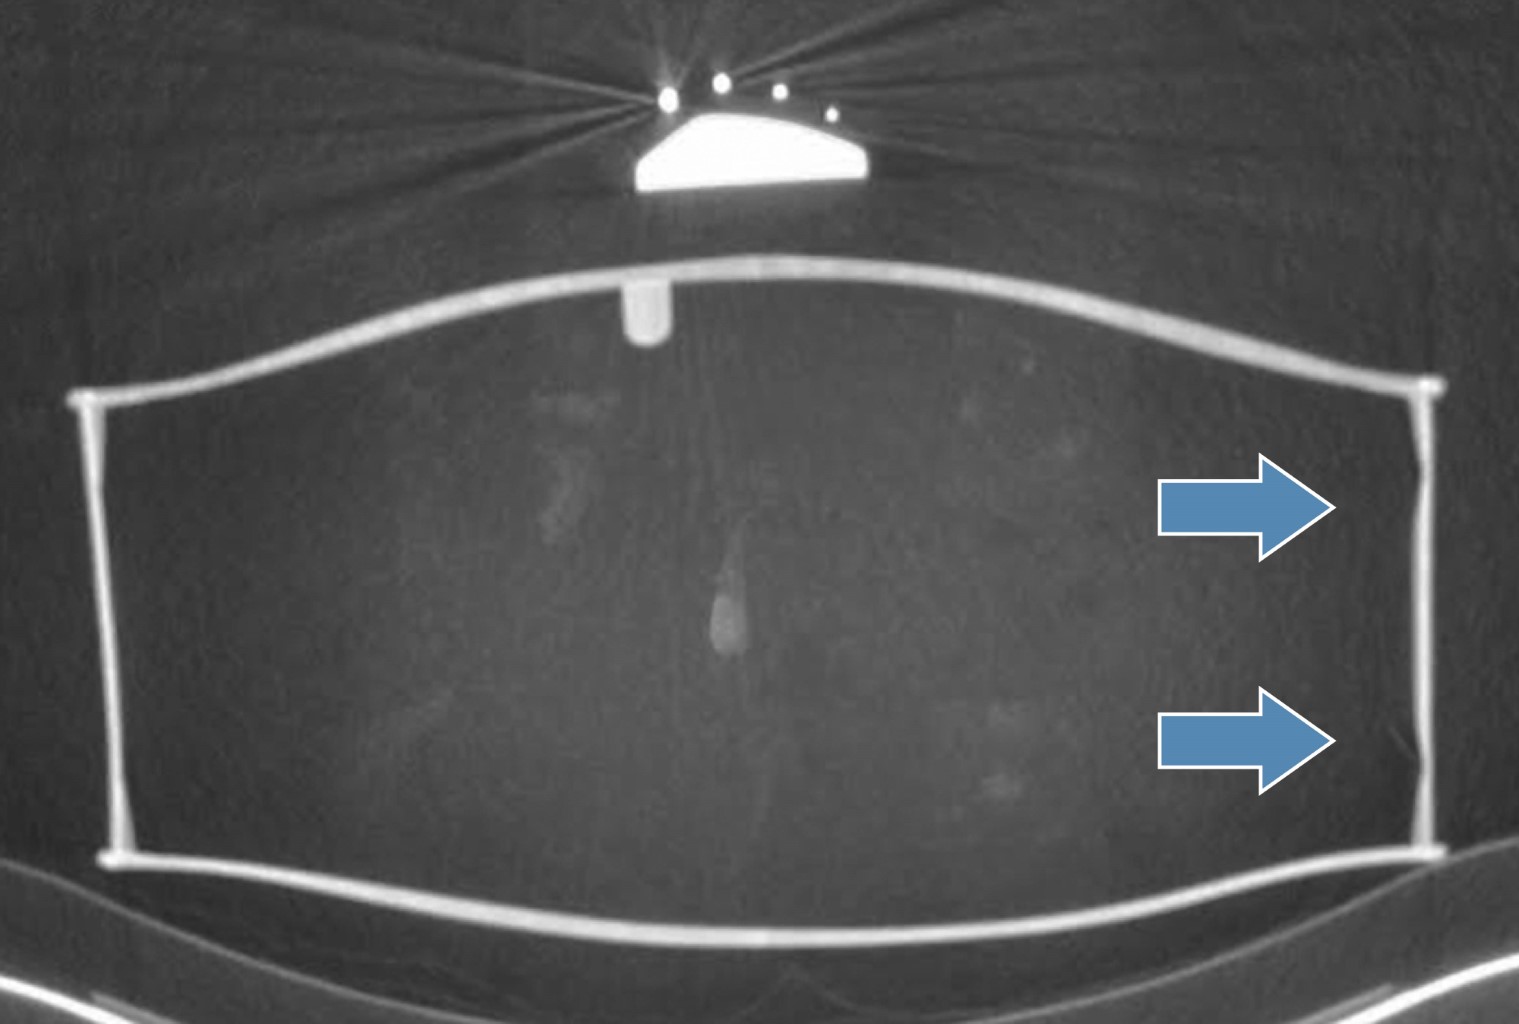

When science and art merge: the usefulness of computed tomography in the study of an ancient string instrument

For many years, radiological studies have been used particularly for the evaluation of paintings on old canvases, with the aim of knowing the presence of other paintings (finished or unfinished), and especially in cases of possible forgeries.The hollow structure of a good number of musical instruments, especially stringed ones, as they are made of wood, make them ideal for study using sectional imaging tools, such as computed tomography. The relatively low number of metallic elements (which cause electronic devices, such as hard beaming) does not generate image degradation, allowing the wall thickness to be accurately obtained, as well as possible cracks or fracture areas that have not involved the visible face of the instrument. The current possibilities for obtaining three-dimensional volumetric images, as well as the assignment of color maps based on density and the possibility of virtual navigation, without the slightest doubt that they can be of great help for the comprehensive assessment of said musical instruments. It is relevant to mention that, in both Germany and Austria, since 1988 there has been a project for the study of ancient instruments, through CT. It turned out to be a unique, fascinating and very enriching experience, where medical science with high technology meets art and history.